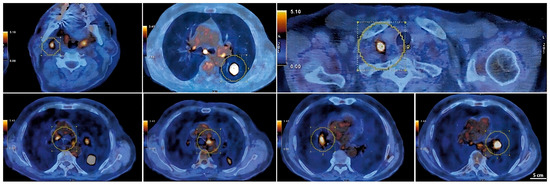

Chest CT showing a large solid nodular formation in the lower left lung lobe.

A PET-CT scan with 18F-FDG performed in March 2023 (Figure 3) revealed intense radiotracer uptake in the nodular lesion of the apical segment of the lower left lung lobe (SUV max 12.5). The scan also showed hypermetabolic lymph nodes in the Barety space (SUV max 4), aorto-pulmonary window (SUV max 5.1), subcarinal region (SUV max 6.4), and bilateral hilar regions (SUV max up to 6 on the left). Additional hypermetabolic lymph nodes were detected in the right supraclavicular region (SUV max 10.2) and in the ipsilateral lateral cervical region (SUV max 5.9), consistent with advanced-stage disease (T2aN3M0) [7].

Figure 3.

PET-CT images of hypermetabolic lymph nodes and the left lower lobe pulmonary lesion.

Serial CT and PET-CT scans over a 24-months period confirmed the absence of new lesions and sustained tumor control. Lymph node involvement, initially extensive, showed significant regression, with some nodes completely resolving. This case suggests that, in select patients, chemo-immunotherapy may induce durable responses beyond standard expectations, warranting further investigation into predictive biomarkers (Figure 5 and Figure S3).

Figure 5.

Reduction of mediastinal lymphadenopathy during treatment with combination therapy and maintenance with atezolizumab.